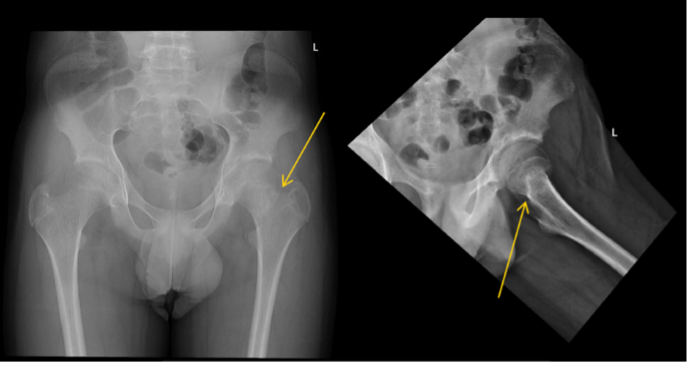

Given the patient’s previous vertebral fractures, low bone density, and recent trauma, fracture was suspected. Initial hip X-ray was reported by the radiology team as negative for signs of fracture. However, after review of the X-ray and the patient’s clinical condition by the pediatrician, a reread of the hip X-ray was requested. A suspected left femoral neck fracture was noted following the reread and the radiology team recommended magnetic resonance imaging (MRI) for confirmation (Figures 1 and 2), which ultimately confirmed the diagnosis.

Figure 1. Bilateral hip X-ray with mildly impacted left femoral neck fracture (yellow arrow).